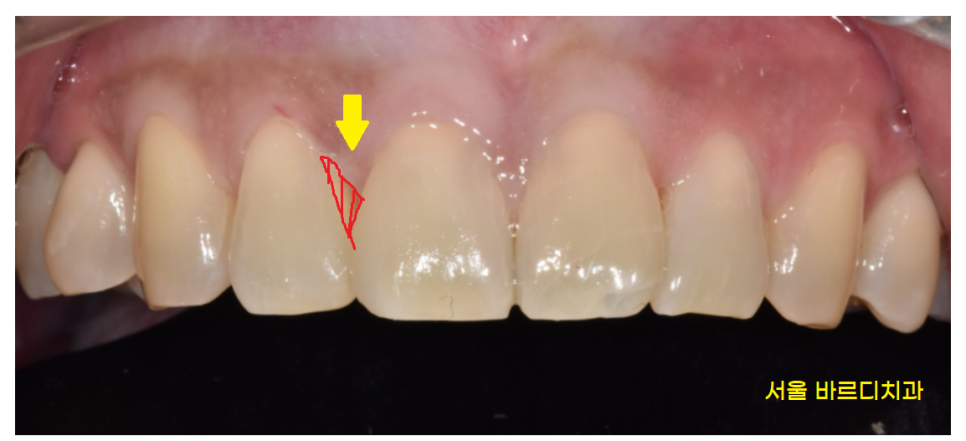

23.01.30

오늘 환자분의 경우

옆 치아와의 공간이 1mm도 채 안되어서

(아주 작은 공간이라는 뜻입니다!)

벌어진 앞니 메꾸기 레진으로 가능했습니다~!

직장인 분이셔서 자주 시간내기 어려우셨기에

당일 레진 치료 진행해드렸는데요~!